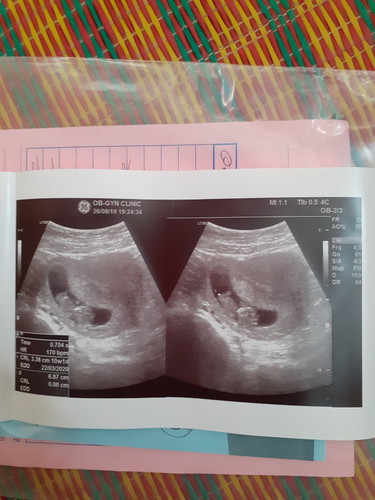

ตอนนี้ ท้องได้ 10 wค่ะ เมื่อวานไปฝากท้องมาค่ะ อยากรู้ว่าดูน้ำหนักเด็กยังไงคะ รบกวนแม่ๆหน่อยนะคะ

หาค่าที่หน่วยเป็นกรัม (g)

วิธีดูจ้า